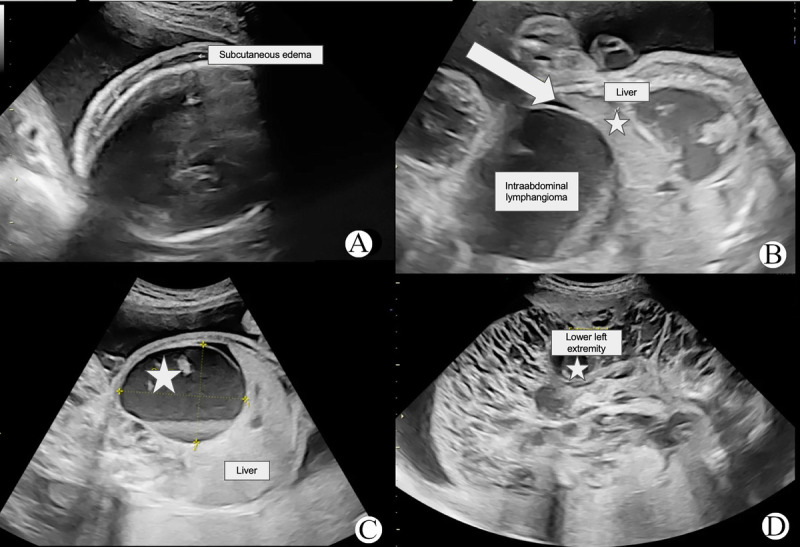

Approximately 75% of lymphangiomas manifest in the head and neck region, with limb and bone involvement observed in only 2% of cases. This case report presents a rare instance of fetal lymphangioma associated with hydrops fetalis, affecting the left lower extremity and abdomen. A 22-year-old secundigravida woman was referred to the gynecology department at 31.2 weeks of gestation. Initial fetal ultrasound revealed a live fetus with a large lymphangioma involving the left lower extremity, gluteal region, and abdomen. Additional ultrasound findings included subcutaneous edema, pericardial effusion, ascites, placentomegaly, and tricuspid regurgitation. Postnatal clinical examination confirmed the diagnosis of lymphatic malformation. Notably, only one other similar case has been reported in the English-language PubMed database. This report adds to the medical literature as a rare instance of prenatally diagnosed lymphangioma-associated hydrops fetalis.

约75%的淋巴管瘤表现在头颈部,仅2%的病例累及肢体和骨骼。本病例报告提出一个罕见的胎儿淋巴管瘤合并胎儿水肿,影响左下肢和腹部。一名22岁的二次妊娠妇女在妊娠31.2周时被转介到妇科。最初的胎儿超声显示一个活的胎儿,有一个大的淋巴管瘤累及左下肢、臀区和腹部。其他超声表现包括皮下水肿、心包积液、腹水、胎盘肿大和三尖瓣反流。产后临床检查确诊为淋巴畸形。值得注意的是,在英文PubMed数据库中,只有一个类似的病例被报道过。本报告增加了一个罕见的产前诊断淋巴管瘤相关积水胎儿的医学文献。